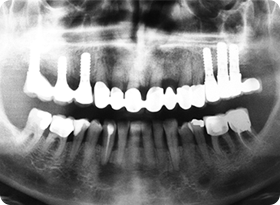

:: 엑스레이 촬영을 통하여 살펴보는 뼈이식 & 임플란트 ::

공간 확보를 위한 엑스레이 촬영

이렇게 임플란트 인공치아 뿌리를 식립하려 하는 자리에

엑스레이 촬영을 통해 공간을 먼저 봅니다.

임플란트 의사 결정

원래라면 저런 어금니 두개가 들어가 있던 자리였죠.

하지만 없으니 임플란트 궈궈!

잇몸뼈 소실 복구

자~ 눈금으로 쉽게 표기해 드릴게요.

보시다시피 옆자리의 잇몸뼈의 높이보다 상당히 내려가

있습니다. 치아가 자리에 없는 동안 많은 잇몸뼈 소실이

원인입니다.

인공치아 뿌리 식립

이렇게 잇몸뼈 이식술을 통해 인공치아 기둥뿌리를 확실히

심어주는 것입니다!